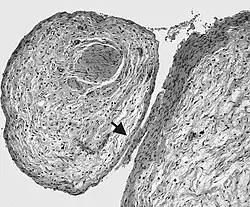

Нейрофибромы

Для данного заболевания характерно появление большого количества нейрофибром, как кожных, так и плексиформных. Кожные нейрофибромы представлены небольшими доброкачественными и ограниченными новообразованиями. Они располагаются подкожно, растут на оболочках мелких нервов кожи. Плексиформные нейрофибромы развиваются на крупных нервах и приводят к нарушению их функций[26]. Также плексиформные нейрофибромы характеризуются своими большими размерами. Встречаются у 30 % больных нейрофиброматозом I типа[22].

Клинически повреждение нерва проявляется хроническими болями, онемением и/или параличами мышц.